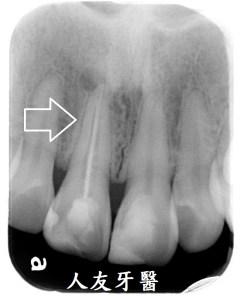

根尖病變一直長膿包還有救嗎?